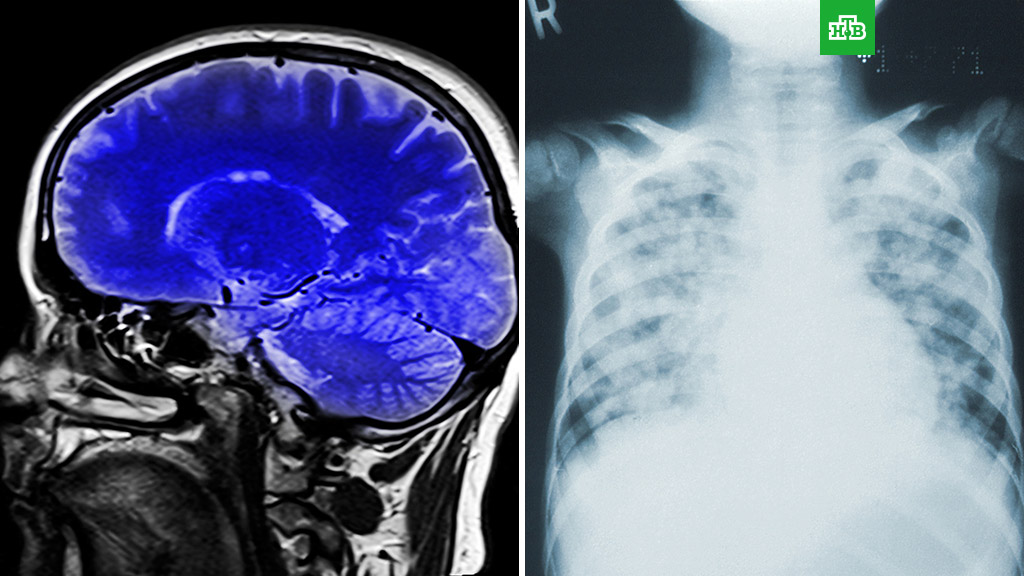

По словам специалиста, медики фиксируют уменьшение объема легких и ухудшение работы мозга у пациентов, которые в тяжелой форме перенесли коронавирус.

Анча Баранова, профессор Школы системной биологии Университета Джорджа Мейсона: «Молодые люди марафон не могут больше бегать, а более пожилые люди одышку испытывают, когда по лестнице поднимаются. Опять же не у всех, а только у тех, кто перенес тяжелую форму, и даже в этом случае не у всех, а только у тех, кому особенно не повезло».

Кроме того, у больных с тяжелым течением наблюдается много неврологических симптомов. Баранова отметила, что у пожилых пациентов были замечены спутанность сознания и дезориентация.

Анча Баранова: «Способность вируса вызывать нейровоспаление сомнений не вызывает. Как долго оно может длиться и как закончится — пока не ясно».

Она также рассказала, что, по словам некоторых больных, даже после того, как их выписывают из больниц, у них остаются усталость и туман в голове.